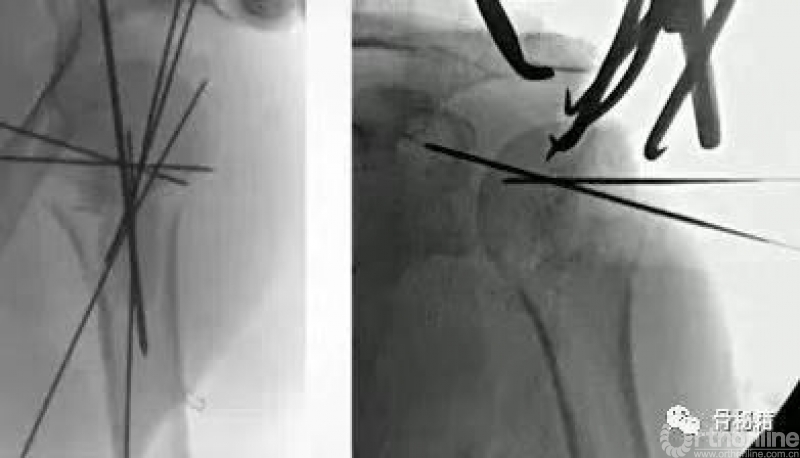

常用的克氏针的临时复位固定技术

可以应用大量的克氏针完成复位,

难复位的时候可以将头临时固定在关节盂上

最关键的就是剩余肱骨头需要进行外翻到合适的位置然后固定

将肱骨头的复位和合适的临时固定是最关键的

在复位好的基础上,植入合适的主钉导针

导针一旦植入,这个手术就完成了一半了